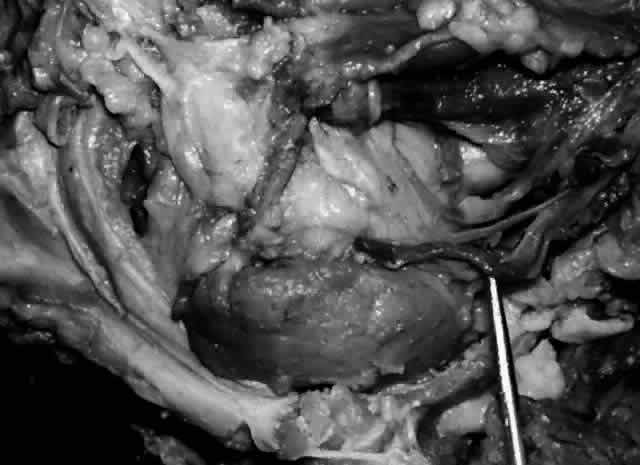

Sanderson and Stasior4 found islands of “peripheral” lacrimal glandular tissue below the lateral canthus unassociated with the main gland in 60% of cadaver specimens (Fig. 8). These peripheral islands of glandular tissue were found less commonly in or above the lateral canthal tendon.

Fig. 8. “Peripheral” lacrimal gland lobules (arrow 1) are seen below the right lateral canthus (arrow 2) and separate from the palpebral lobe of the lacrimal gland (arrow 3). (Courtesy of James Sanderson, MD, Orkan Stasior, MD, and George Stasior, MD)